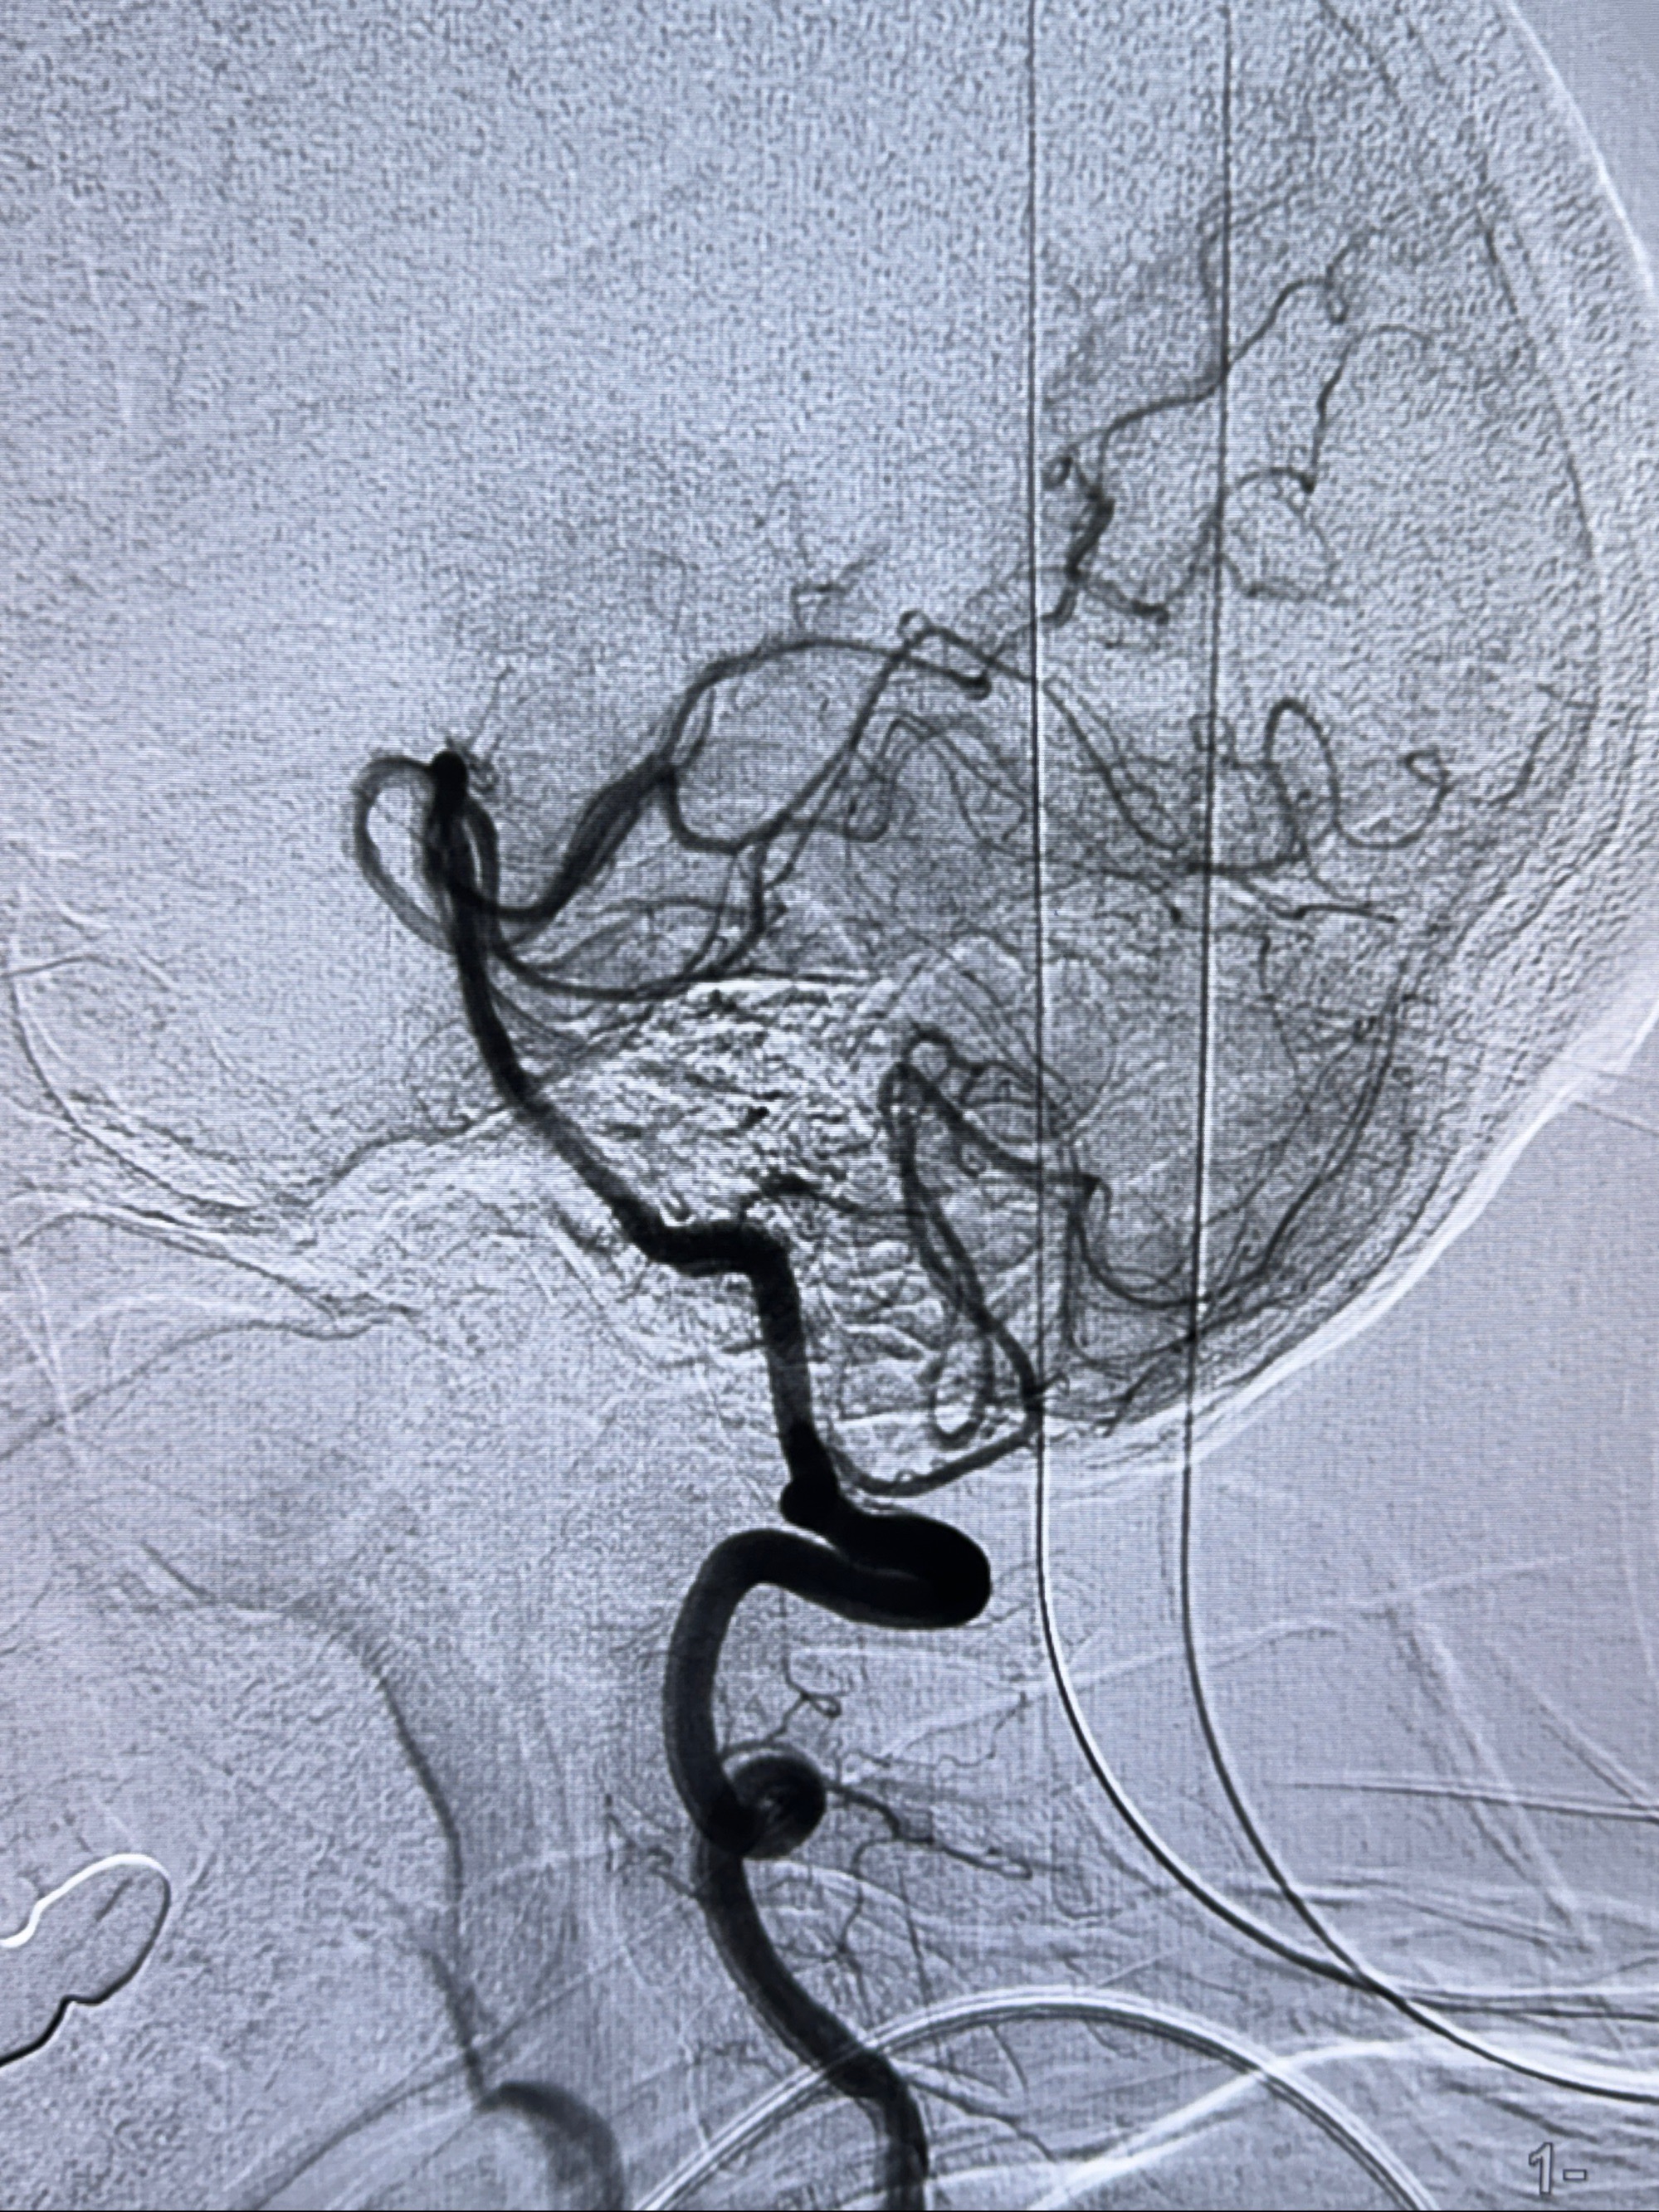

2023-12-04全麻下行支架辅助治疗

S-AB4-20mm

麻醉苏醒佳,遵嘱动作

术后即刻CT